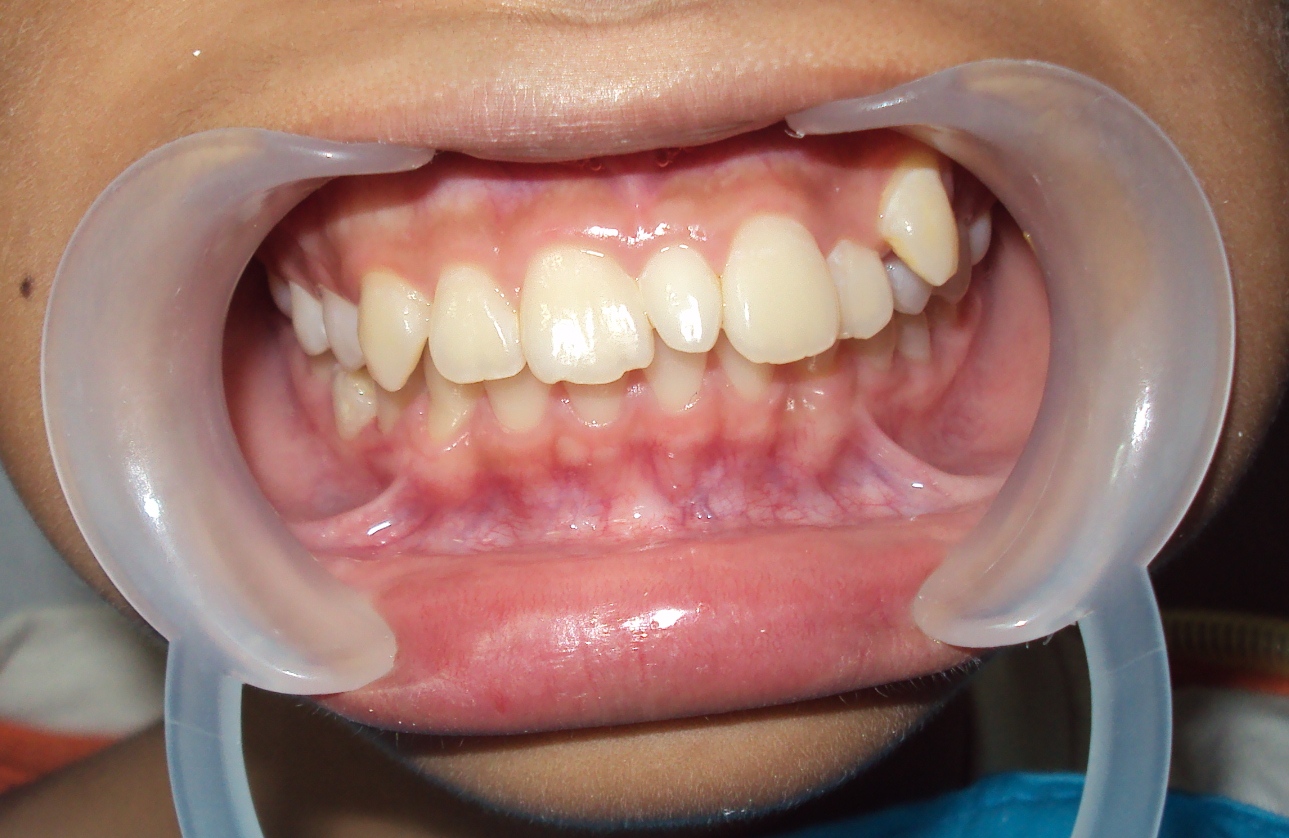

Фото

Рекомендуем ознакомиться с фотографиями ротовой полости пациентов с аномалиями для более глубокого понимания проблемы.